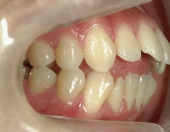

主訴:奥歯で噛んだときに前歯が噛み合わない

━━ 当院で働いている池谷彩乃さんが、前突および開咬を舌側ワイヤー矯正で治療しました。

高校時代には、歯並びを改善しようと様々な矯正サイトを閲覧し、自分自身が開咬であることを知りました。開咬とは、上下の歯を噛み合わせた時に前歯に隙間ができることを言います。そういえば、麺を前歯で噛みきること、ハンバーガーにガブッと噛みつくことができませんでした。

2年を少し過ぎたころには歯並びが良くなり、開咬もだいぶ改善されました。結婚式を予定していたため早期終了をさせていただきましたが、開咬が治ってハンバーガーをガブッと噛みきることができるようになって、とっても嬉しいです。式でもきれいな歯並びで、思いっきり笑うことができました。